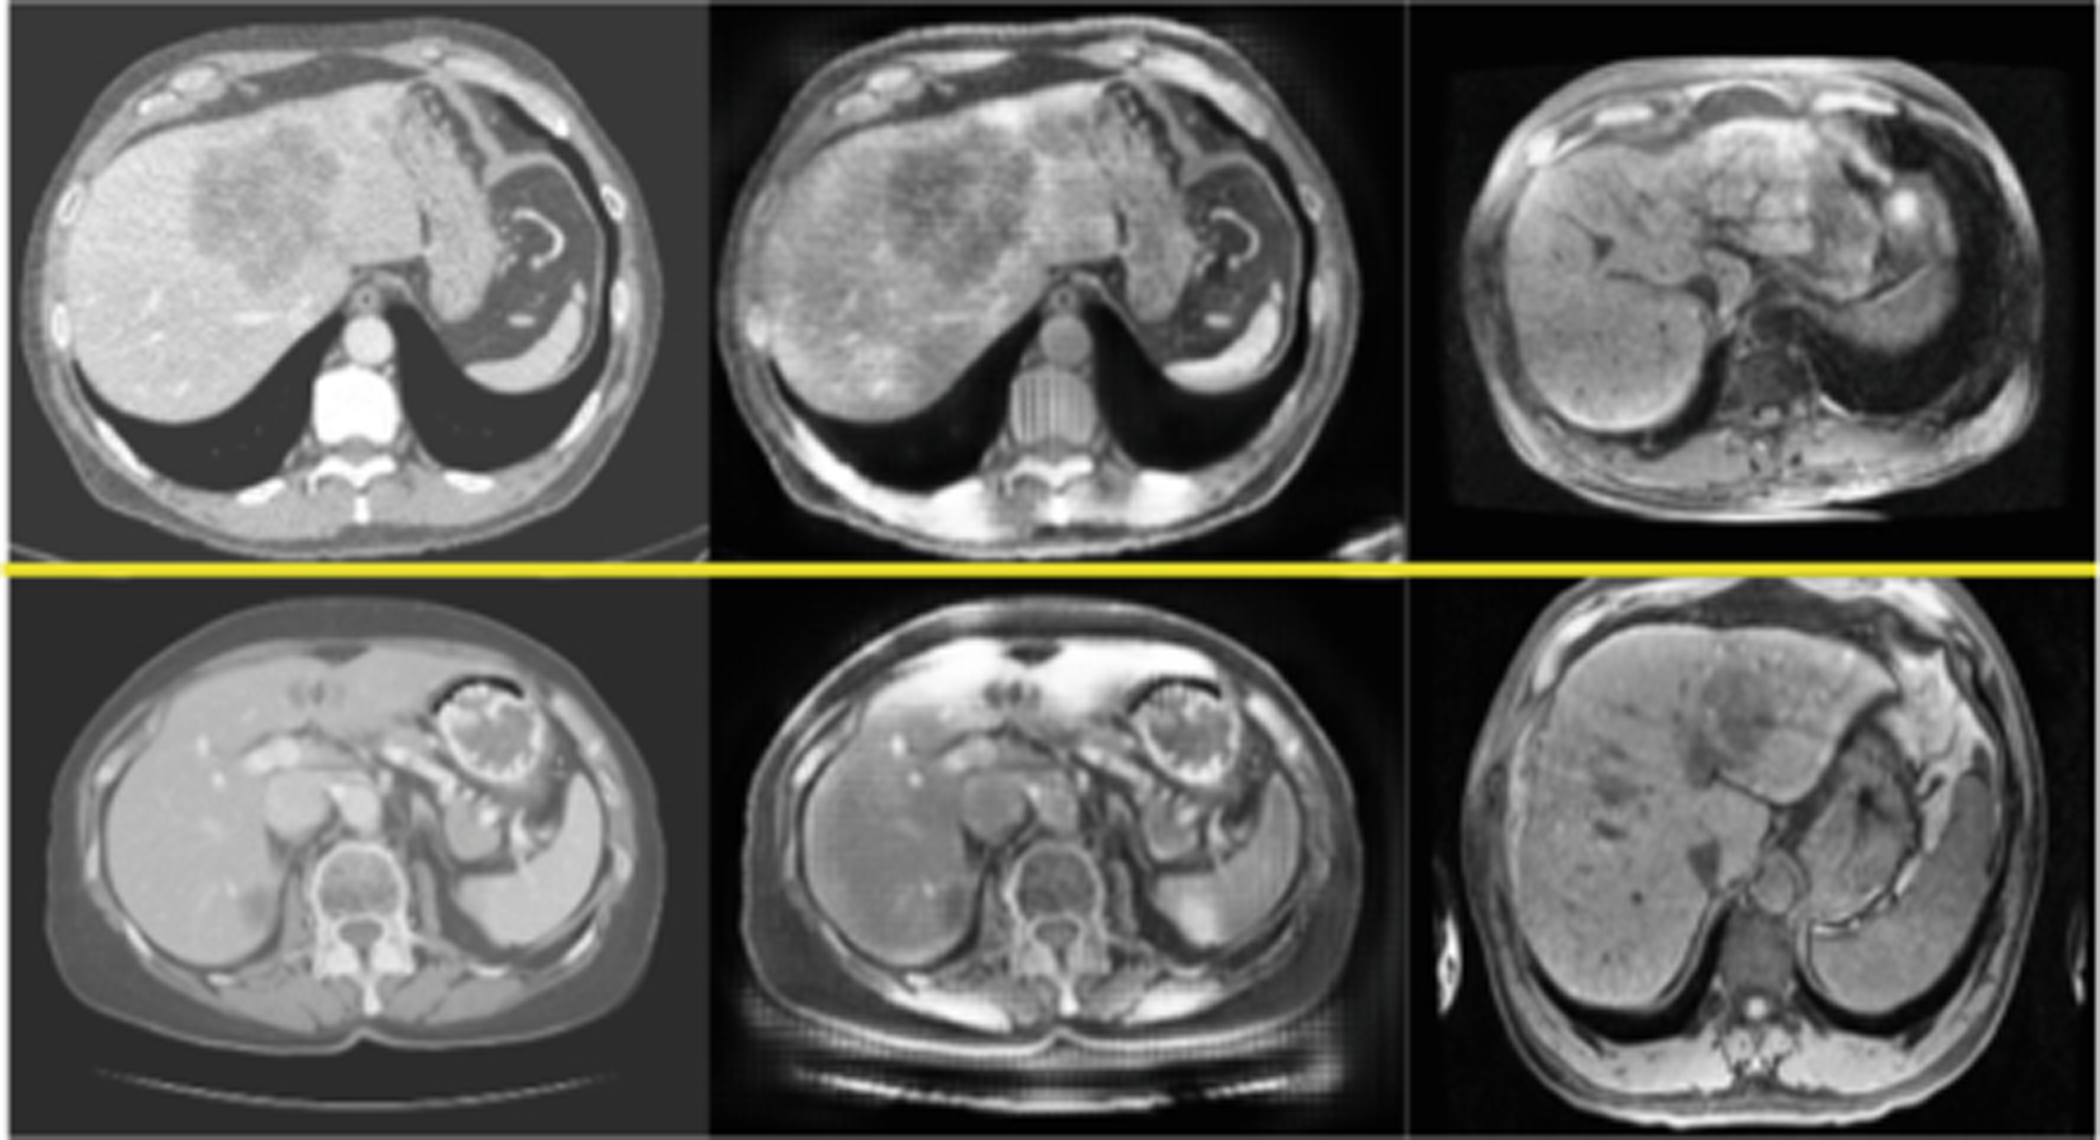

Given the significant domain shift, cross-modality domain adaptation is quite difficult (see Fig. 1). One promising approach utilizes CycleGAN, a pixel-wise style transfer model, for cross-modality domain adaptation in a segmentation task [3]. Compared to feature-based domain adaptation, it does not necessarily maintain the semantic feature-level information. More importantly, the cycle-consistency loss implies a one-to-one mapping between source domain and target domain and leads to lack of translated output diversity, generating very similar images. It thus fails to represent the complex real-world data distribution in the target domain and likely degrades the performance of segmentation or other follow-up analysis [5].

Fig. 1.

Images and histograms of liver (yellow) and whole image (blue). From left to right: CT, multiphasic MRI sequence at three time points (pre-contrast, 20 s post-contrast i.e. arterial phase, 70 s post-contrast i.e. portal venous phase) (Color figure online)